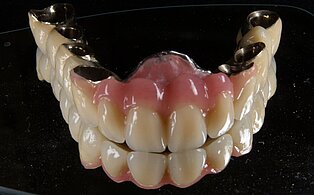

Keramik auf Metall

Nichtedelmetal NEM und Keramik

Meisterarbeit von Peter Dengel